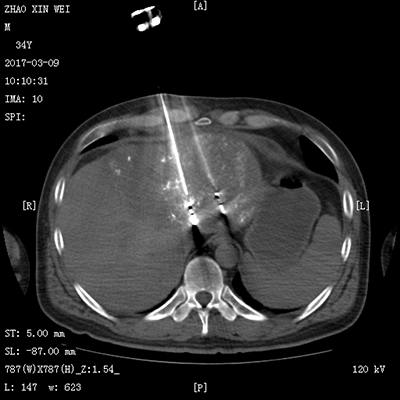

![]() | ![]() |

| (脾功能亢进的介入治疗) | (食道支架植入术) |